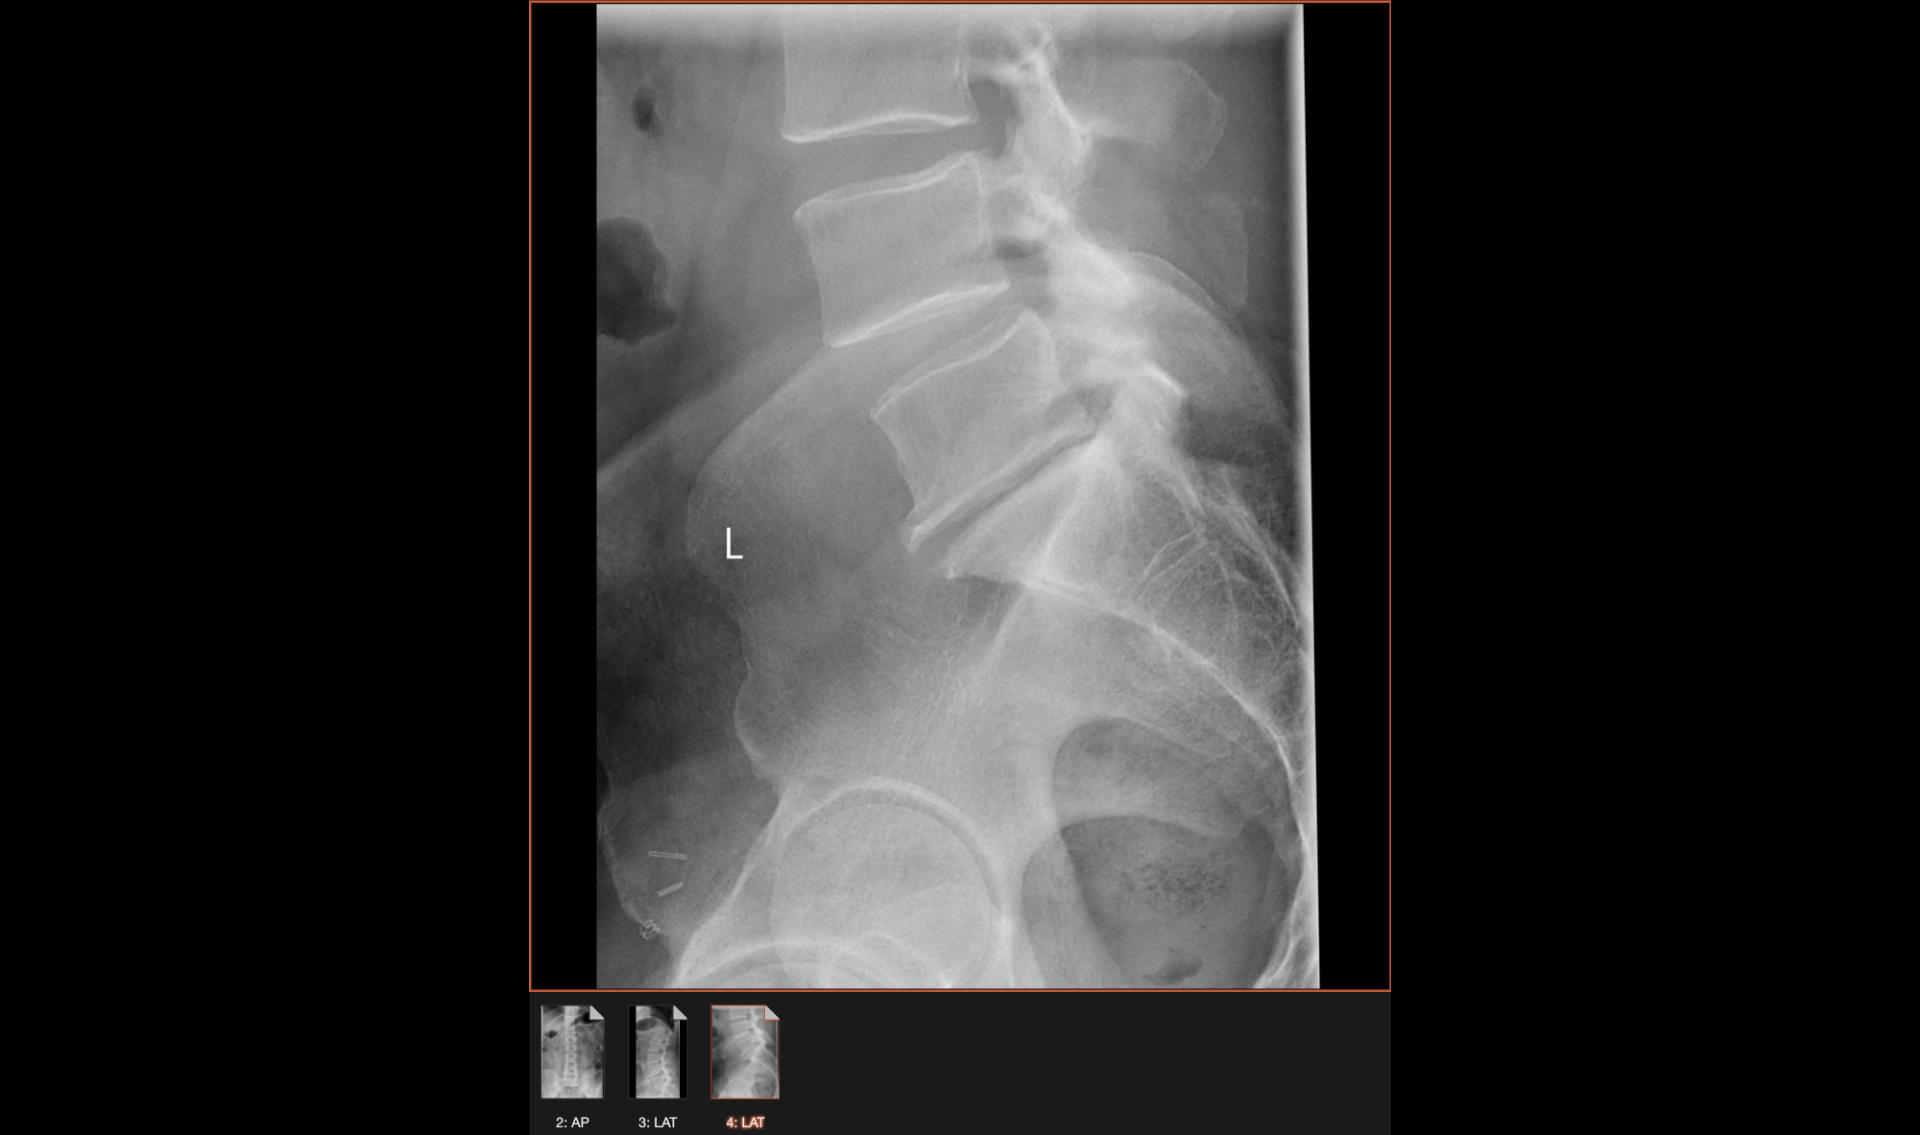

MRI Scan

Oh! A lot has happened since the last post. I saw a doctor, got an injection in my hip (that did not work and offered no relief) and then I got an increase in my medication, and then I got an MRI and then another increase in my medication (sigh) and sometimes I have to take out-of-state medication.

MRI Imaging

MRI Animated GIF file

So what’s next? Well, I got an EMG (electromyography) and the good news is my nerves are not damaged. So I saw another doctor this week and we’re going to move forward with getting me two injections into each side of my spine because they can’t do just one from the back due to the spacing. (Eww.)

The thing about this pain I have now, which was originally diagnosed as sciatica, is that it’s become so unpredictable, and so painful. I guess the discs in my lower back and garbage, and it’s causing nerve pain, and it’s so, so bad. Some days I am in pain for a few hours, and some days it’s 10+ hours. When the pain is gone I am mostly fine, unless I sit in a desk chair for too long. I’ve been doing the “set a timer, sit and work for 20 minutes, then get up to stretch and move” routine for months now.